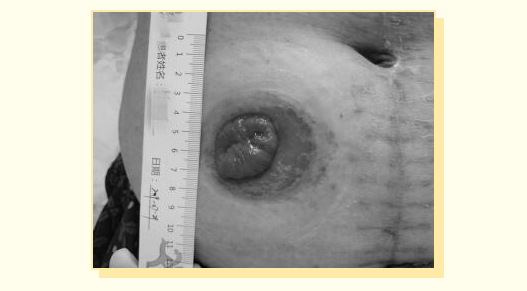

刘晓丽经过认真细致评估,判断阿姨造口袋渗漏的主要原因是造口内陷,周围皮肤问题是粪便污染浸渍所致。于是按照流程进行彻底清洁-使用护肤粉-喷洒保护膜-涂抹防漏膏-凸面造口底盘纠正造口内陷-连接造口袋等一系列规范操作,同时为家属详细讲解护理要点。